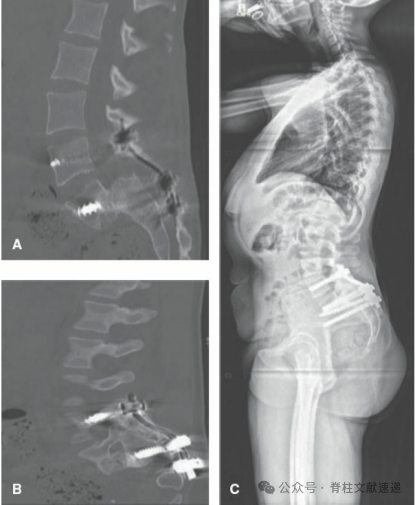

术后影像资料

原位融合较复位技术简单,核心理念是从S1穿螺钉通过骶骨岬到达L5椎体实现固定。操作和前面一样,显露、置钉、减压(若患者存在神经症状),采用L4椎弓根螺钉、S1螺钉从骶骨岬打入L5椎体进行串联固定(连续透视或导航下),S2AI或髂骨螺钉固定,后外侧植骨融合。如下图。该技术最大的问题是不融合率较高,越20%。部分患者腰椎滑脱会继续进展,而在此手术的难度更大,风险更高。